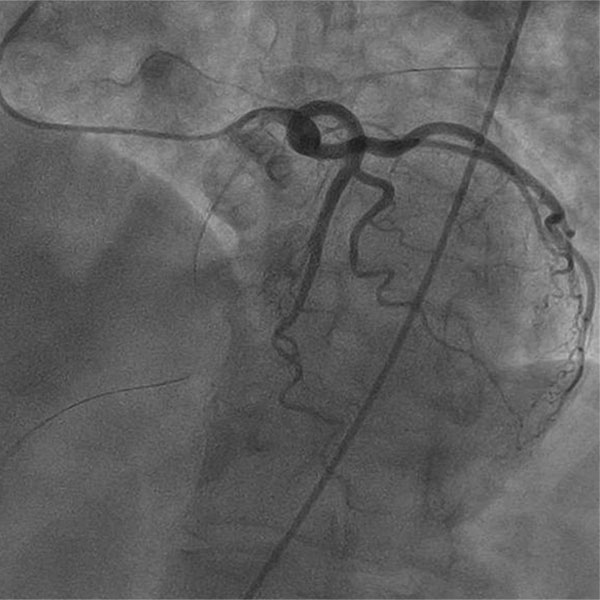

A 73-year-old female with a history of coronary artery bypass grafting (CABG) including LIMA to distal LAD, SVG to D1, and SVG to OM2, presented with recurrent, disabling chest pain.